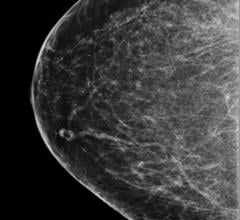

May 3, 2023 — ScreenPoint Medical announced today that its Transpara breast AI has surpassed 4 million mammograms (2D ...